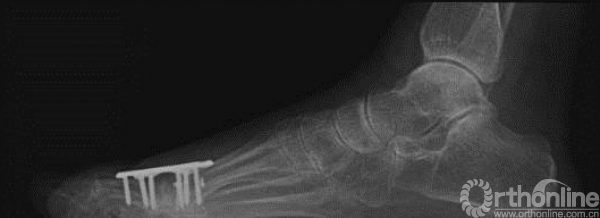

17、 术后X线

四、术后3个月随访